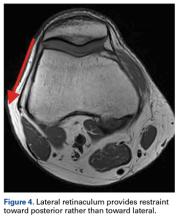

It has been found to provide an important restraint against LPD.18-20 In primary LPD, the MPFL has been found ruptured or severely damaged in more than 90% of cases, most often near the femoral insertion.18,21-23 In patients with an elongated, insufficient MPFL, the patella may dislocate laterally without rupturing the MPFL. Another soft-tissue structure that contributes to patellar stabilization is the lateral retinaculum, which provides a restraint toward posterior rather than lateral (Figure 4). Cutting the lateral retinaculum would further decrease patellar stability in most cases.18,24-26